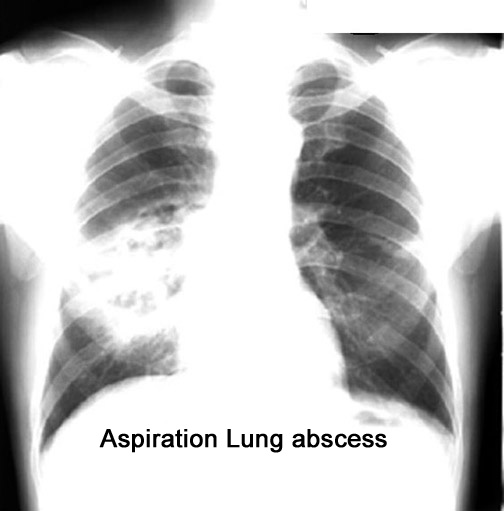

Labeled Image How do you distinguish septic emboli from aspiration pneumonia?

Case 27 Labeled Image How do you distinguish septic emboli from aspiration lung abscesses?

Labeled Image What are the common segments for aspiration lung abscess?